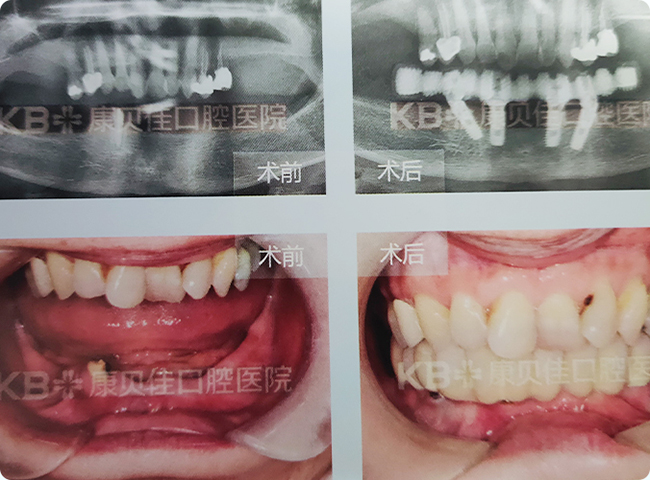

陆先生 87岁

10年前上下颌多颗牙逐渐脱落,未予处理。因影响咀嚼导致消化不良等情况要求种植。考虑到患者年龄较大,且缺牙时间长导致牙槽骨萎缩严重,在拔除没有保留价值的三度松动牙后,采用种2颗恢复半口的种植半固定方法修复。

治疗方案:

上颌2颗恢复半口种植半固定修复 下颌2颗恢复半口种植半固定修复